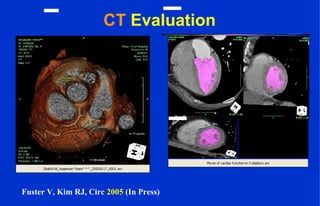

CT Evaluation

Fuster V, Kim RJ, Circ 2005 (In Press)